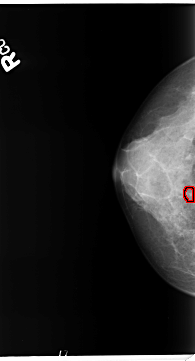

B_3363_1.RIGHT_MLO

RIGHT_CC LINES 4688 PIXELS_PER_LINE 2528 BITS_PER_PIXEL 12 RESOLUTION 50 OVERLAY

FILE: B_3363_1.RIGHT_MLO.OVERLAY

TOTAL_ABNORMALITIES 1

ABNORMALITY 1

LESION_TYPE CALCIFICATION TYPE PLEOMORPHIC DISTRIBUTION CLUSTERED

ASSESSMENT 4

SUBTLETY 3

PATHOLOGY BENIGN

TOTAL_OUTLINES 1

BOUNDARY